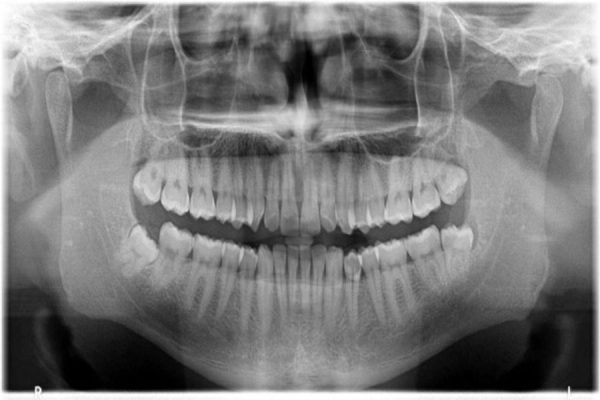

At Manubhai Shah Medical & Research Centre, we proudly present state-of-the-art OPG (Orthopantomogram) X-ray services. An OPG (Orthopantomagram) is a panoramic scanning dental X-ray of the upper and lower jaw. It is also sometimes called by the proprietary name Orthopantomagraph or Panorex. It shows a flattened two-dimensional view of a half-circle from ear to ear. Panoramic x-rays allow images of multiple angles to be taken to make up the composite panoramic image, where the maxilla (upper jaw) and mandible (lower jaw) are in the viewed area. The structures that are outside the viewed area are blurred. At some stage in your dental treatment, your dentist will likely take an OPG.